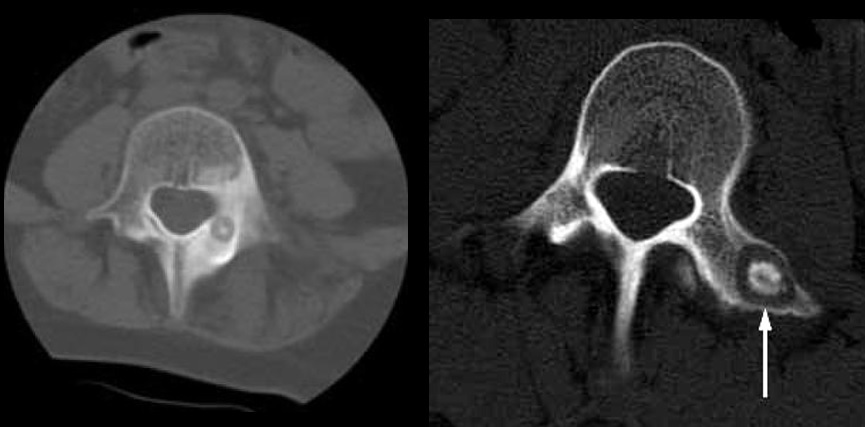

11

Q

Qual diagnóstico?

A

Nidus < 1,5

Dx: osteoma osteóide

Nidus < 1,5 cm